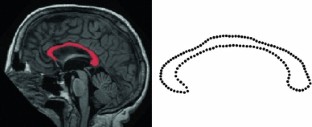

This paper develops the theory of geodesic regression and least-squares estimation on Riemannian manifolds. Geodesic regression is a method for finding the relationship between a real-valued independent variable and a manifold-valued dependent random variable, where this relationship is modeled as a geodesic curve on the manifold. Least-squares estimation is formulated intrinsically as a minimization of the sum-of-squared geodesic distances of the data to the estimated model. Geodesic regression is a direct generalization of linear regression to the manifold setting, and it provides a simple parameterization of the estimated relationship as an initial point and velocity, analogous to the intercept and slope. A nonparametric permutation test for determining the significance of the trend is also given. For the case of symmetric spaces, two main theoretical results are established. First, conditions for existence and uniqueness of the least-squares problem are provided. Second, a maximum likelihood criteria is developed for a suitable definition of Gaussian errors on the manifold. While the method can be generally applied to data on any manifold, specific examples are given for a set of synthetically generated rotation data and an application to analyzing shape changes in the corpus callosum due to age.